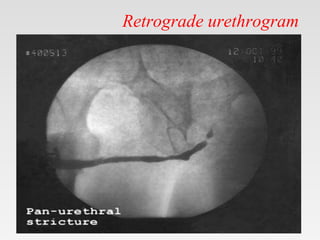

• Retrograde urethrogram

• Antegrade cystourethrogram

Retrograde urethrogram